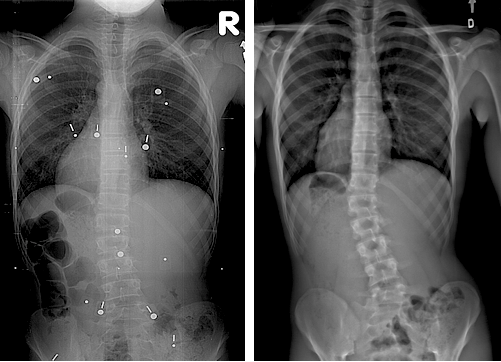

Refer to caption

(a)

(b)

Figure 1: Examples of similar baseline 3D reconstructions with different longitudinal outcomes. (a) A non-progressive case. (b) A progressive case.